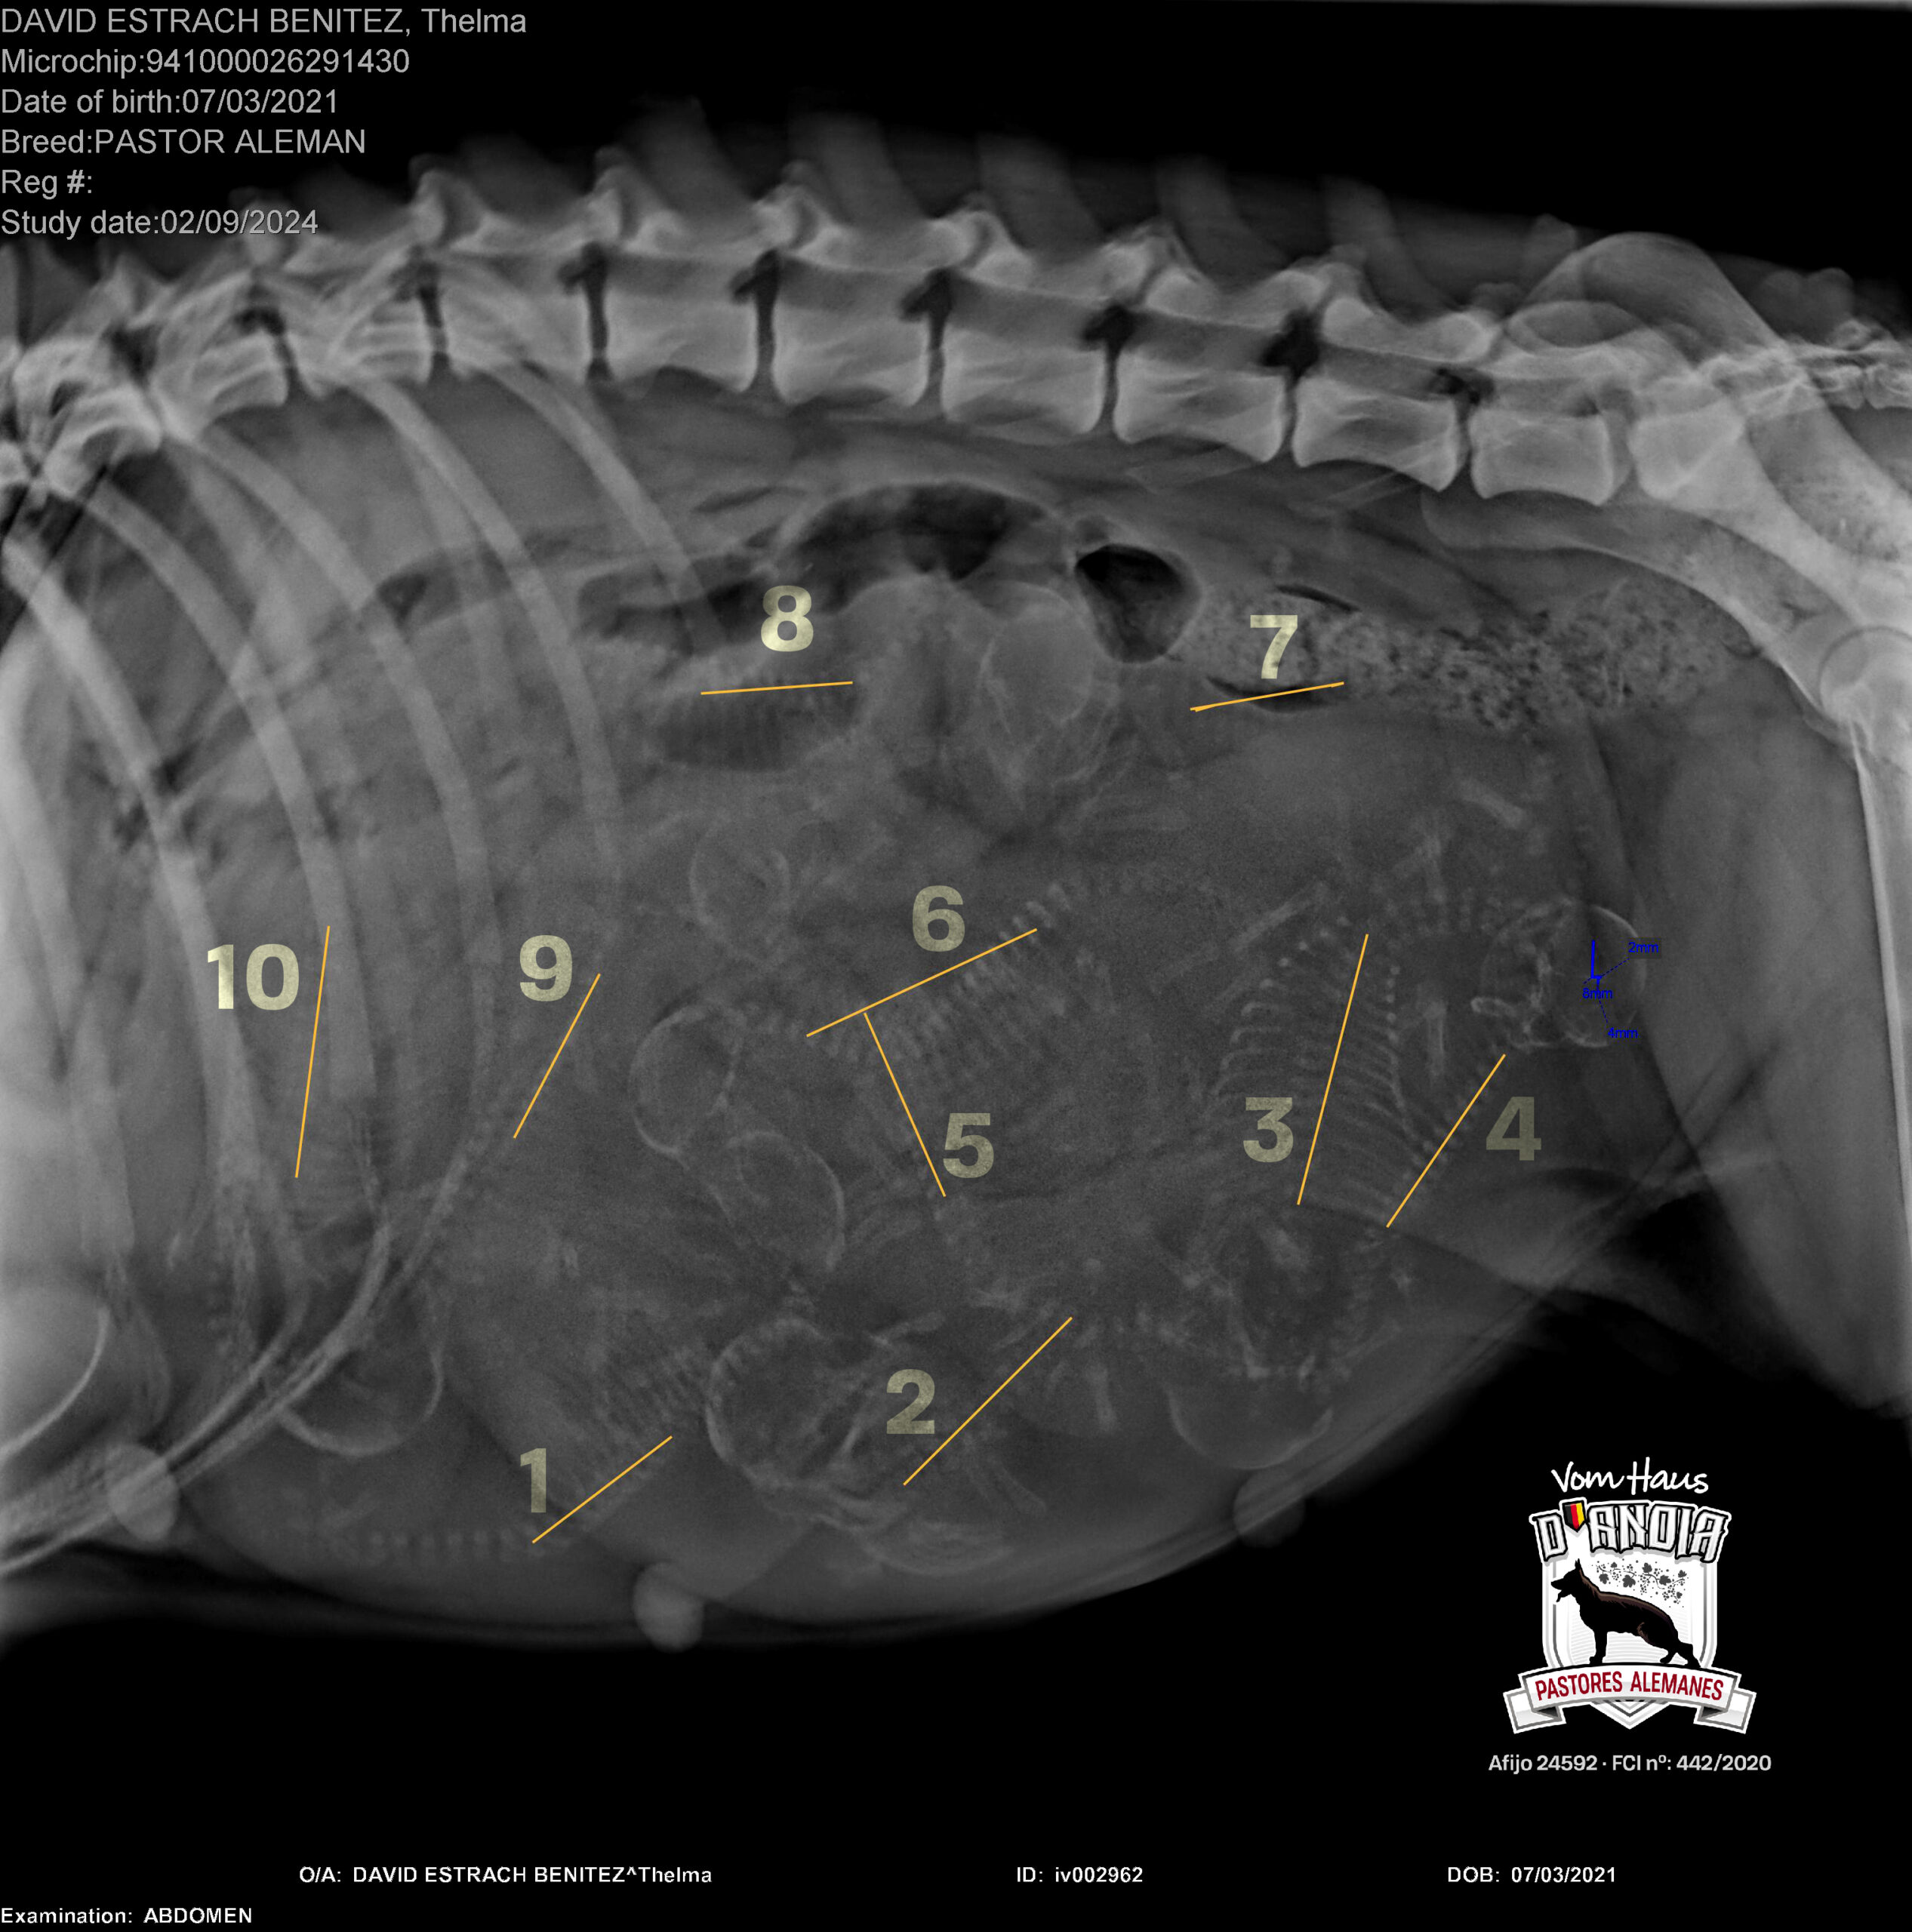

Thelma (Turca de Usurbe)